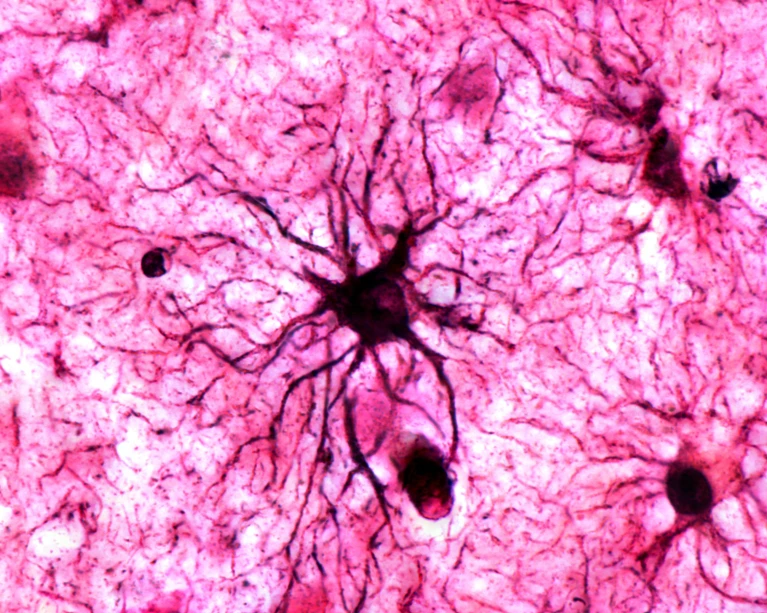

Мы привыкли думать, что всё в мозге — дело рук нейронов: именно они якобы отвечают за мысли, чувства и воспоминания. Но тут на сцену внезапно выходят… астроциты! Уже запомнил? Нет? Тогда держись: эти "вспомогательные" клетки, которых в мозге даже больше, чем нейронов, были считались всего лишь обслуживающими персоналом. Типа доставки энергии и уборки мусора. Но вот — сенсация: именно они помогают «запекать» особые, эмоциональные воспоминания так, чтобы они буквально въедались в мозг.

Учёные из Японии решили не просто наблюдать за мышами, а посмотреть, как активируются астроциты прямо во время вспоминания ярких эпизодов.​

3. И вот тут бомба: на повторном "возвращении" активируются не только нейроны, но и астроциты! При первом обучении — ничего, а вот когда событие становится значимым, они словно получают «разрешение» закрепить воспоминание.